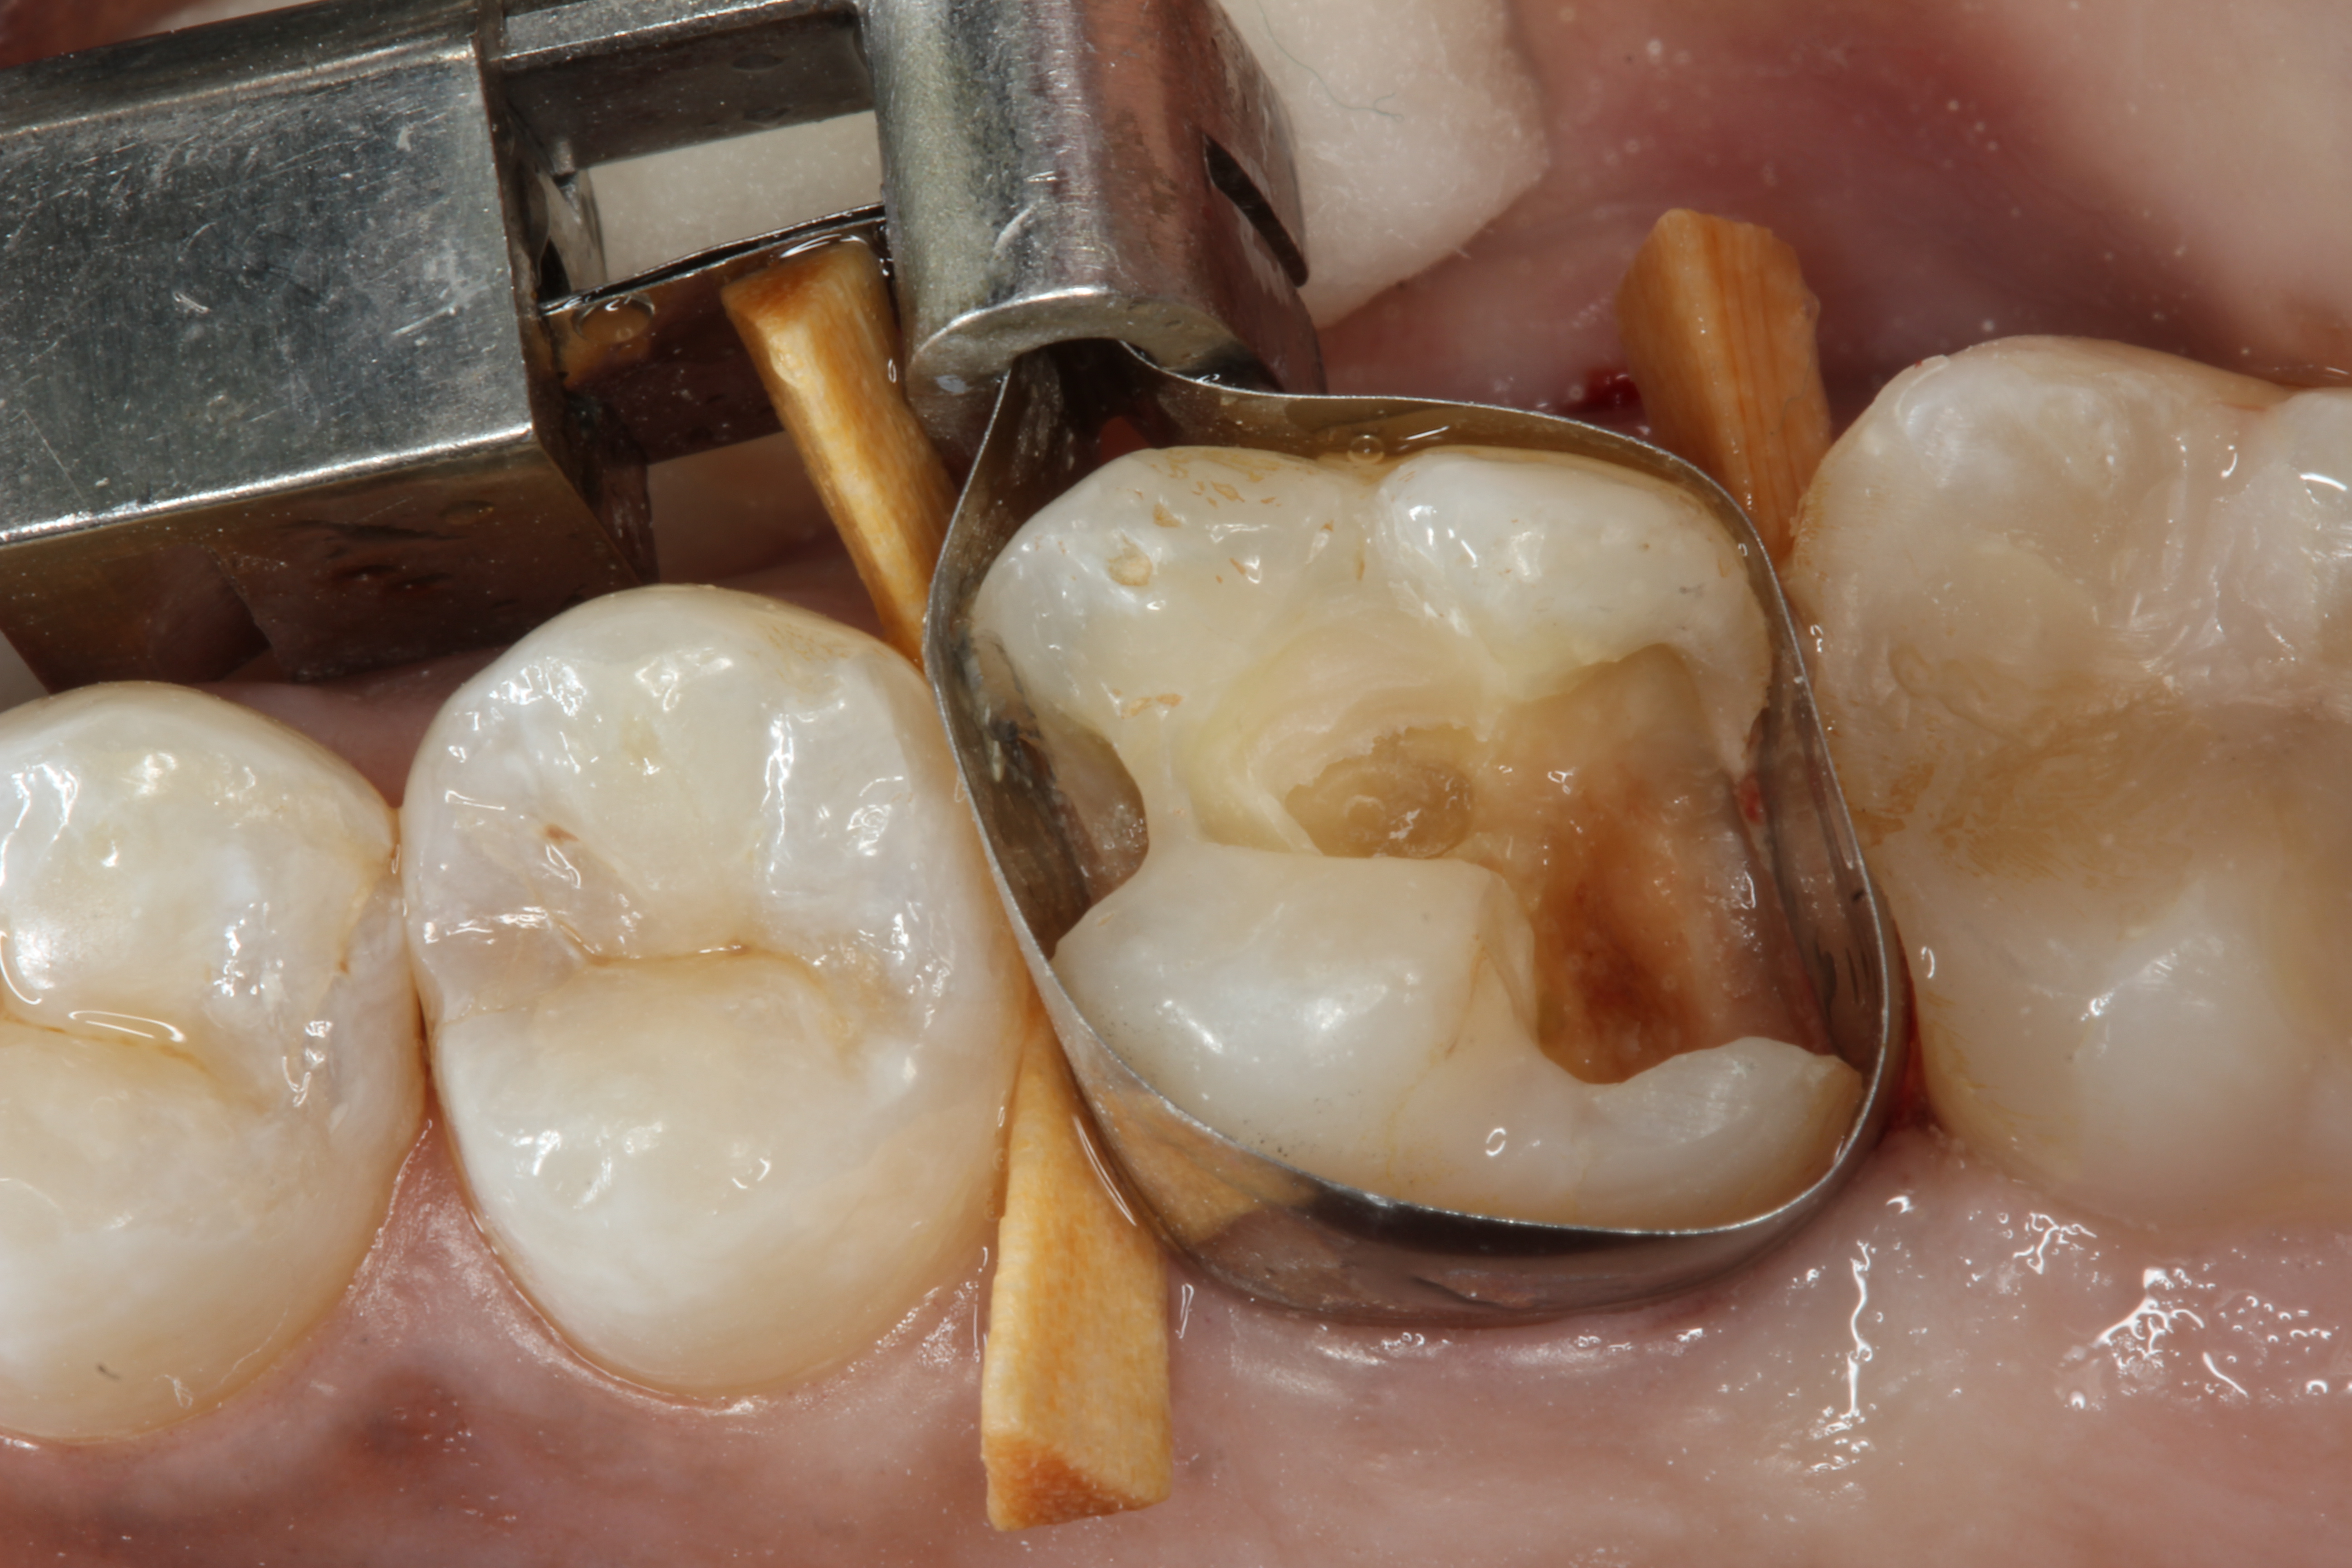

To determine how much to remove, it is important to understand the difference between infected dentin and affected dentin. The infected layer of dentin is highly demineralized, is physiologically unable to remineralize, and contains irreversibly denatured collagen fibrils with a virtual disappearance of cross-linkages.18 It contains bacteria and degraded collagen that cannot be remineralized. On the other hand, the affected dentin has a minimal concentration of bacteria, and the collagen network is still viable.19 Clinically, affected and infected dentin are differentiated by their hardness. Infected dentin is soft and can be easily removed with a spoon excavator (Figure 4). Affected dentin is leathery and requires firm pressure to be removed with a spoon excavator (Figure 5).20

Fig 4. Removing soft infected dentin.

Figure 4

Fig 5. Removing firm affected dentin.

Figure 5